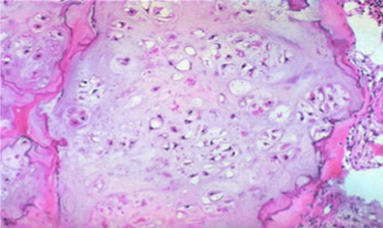

Chondrosarcoma Morphology

Composed of glistening gray white translucent cartilage nodules along with gelatinous or myxoid areas

Neoplastic cartilage/chondrocytes infiltrate marrow space

Spotty calcifications in matrix

Destroy cortex & extend into soft tissue around bone